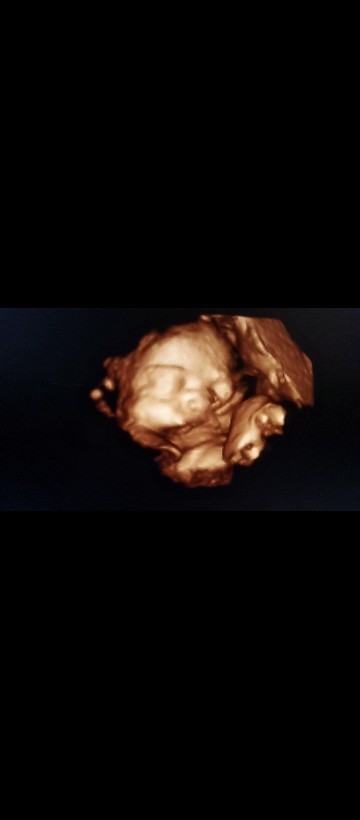

Hpl 30maret22

Ada gak bunda dsini hpl 30maret.. Kalo ada apa yg d rasain.. Kalo aku bokong dan selangkangan udah nyeri2.. Alhamdulillah ini usg 33w6d.. Bbj 2,5kg Hpl maju jadi tgl 15maret karena memang harus Sc ini anak ke 3..yang 2 dulu karena sc semua.. Semoga bunda2 semua yang lagi menanti kelahiran si buah hati tercinta selalu diberi kesehatan dan kelancaran.. Aminn